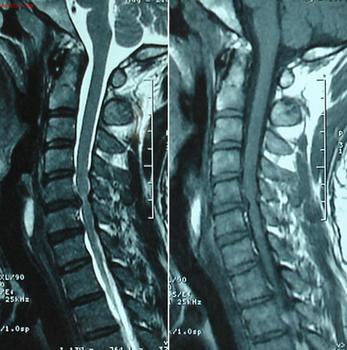

强直性脊柱炎会发生与什么有关